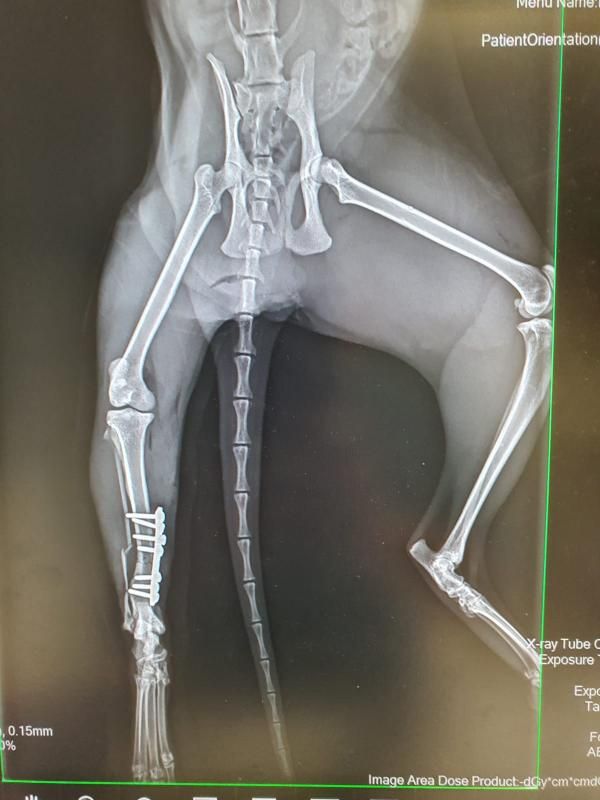

Nymera kam über die Polizei zu uns. Sie wurde von ihrem Besitzer einige Zeit weggesperrt und unversorgt zurückgelassen. Zu allem Übel haben wir festgestellt, dass das rechte Hinterbein gebrochen ist. Am 30.10.2025 haben wir einen Kliniktermin und hoffen sehr, dass sein Bein gerettet werden kann. Also heißt es "Daumen drücken"!